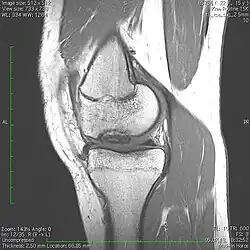

Die Erkrankung kann zufällig auf einem Röntgenbild entdeckt werden, das nach einem Unfall von der Knieregion, vom Sprunggelenk oder vom Ellbogen angefertigt wird. Bei typischen Beschwerden von aktiven Kindern und Jugendlichen kann mit einem solchen einfachen Röntgenbild die eindeutige Diagnose schon gestellt werden, weil der veränderte Knochen unterhalb der Gelenkoberfläche an typischer Stelle in der Oberschenkelrolle am Knie identifiziert werden kann. Manchmal kann eine sogenannte Tunnelaufnahme mit gebeugtem Knie die Schädigungszone noch besser zeigen. Zur genaueren Analyse sollte eine Kernspintomographie (MRT) durchgeführt werden. An den dabei erzeugten Bildern lässt sich die Lage und Größe des Befundes, die Tiefenausdehnung und vor allem eine Beteiligung des darüberliegenden Knorpels genau ausmessen. Es sind damit auch Aussagen zur Stabilität des Befundes zu treffen. Daraus ergeben sich dann entscheidende Anhaltspunkte für therapeutische Konsequenzen. Für die Verlaufsbeurteilung der Erkrankung eignet sich am besten das MRT, aber ggf. auch wieder die einfache Röntgenuntersuchung. Aufgrund der extrem hohen Kosten für das MR in den USA werden die Verläufe dort bis heute weitgehend nur mit Röntgenbildern dokumentiert, was zu eigenen Empfehlungen zur Verlaufsbeurteilungen führt. Generell wären aber die MR-Untersuchungen das Verfahren der Wahl. Sie erlauben eine differenzierte Beurteilung der unterschiedlichen Kriterien für Ausheilung, Instabilität und drohende Dissektion. Untersuchungen mit Sonographie können zuverlässige, aber nur orientierende Befunde am Femurkondylus erheben. Es ist damit zum Beispiel ein schneller, kostengünstiger und sicherer Ausschluss des Befalls auch der Gegenseite möglich.